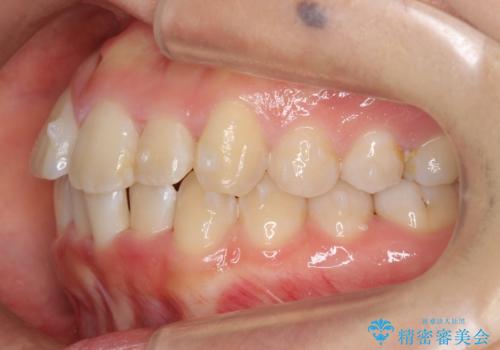

上下の前歯のがたつき 歯を抜かずに矯正

- 上下の前歯のがたつきを主訴に来院。

歯を抜かずに前歯を揃えています。

奥歯を後ろに下げたりなどはしていません。

奥歯を外に広げ、前歯中心に歯を少し削っていますが、健康には問題ない範囲で行なっています。